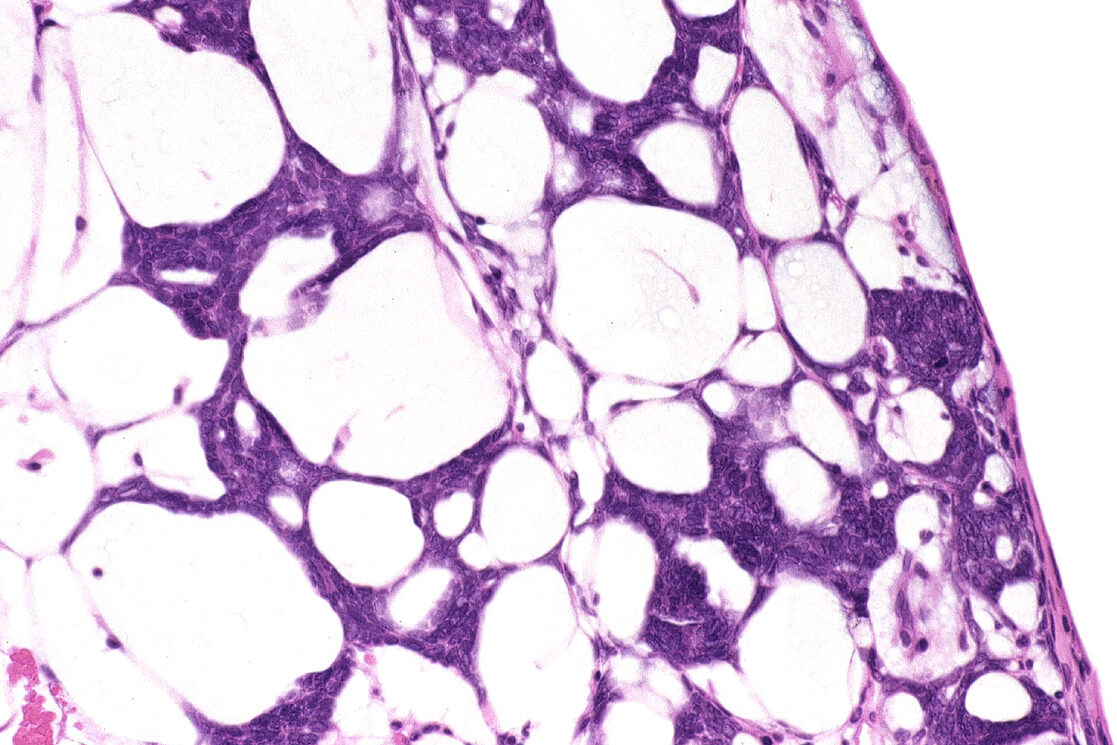

18. Some Cells Never Fully Mature

In species that regenerate, certain cells stay immature and ready to change roles. A scientist once compared them to “workers who never learn only one job.” These cells remain open to instruction, becoming whatever the body needs. Mammals encourage cells to specialize completely, which helps build complex bodies but limits their flexibility. Regrowing a limb requires cells that stay simple enough to adapt. Animals that regenerate preserve these adaptable cells into adulthood. It is almost like they keep a group of generalists on standby, waiting to fill any role the body might suddenly need.